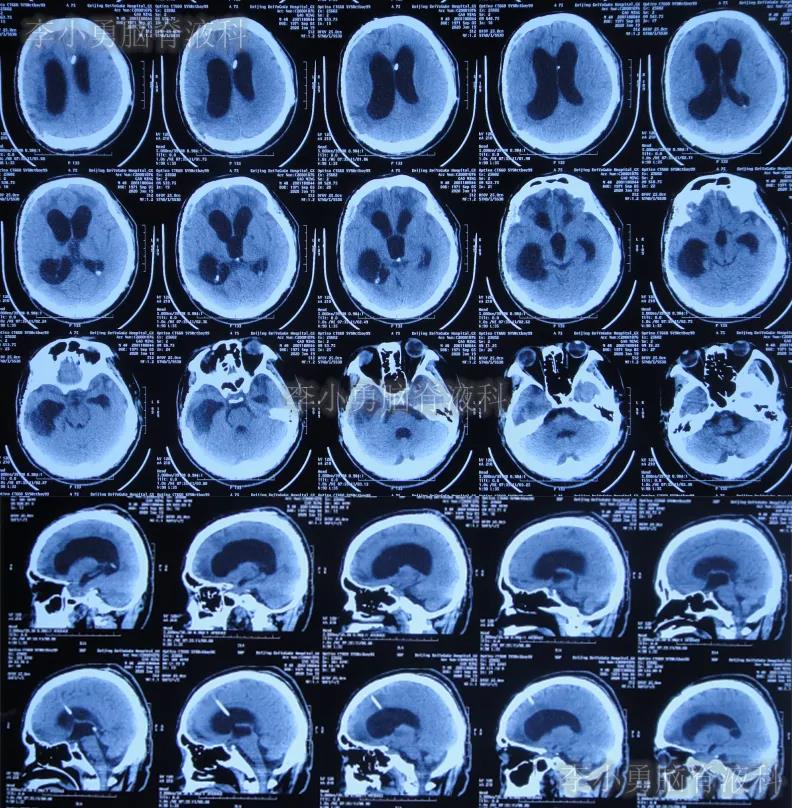

入院次日查头颅CT示颅骨修补术后,脑室引流后仍脑积水(图-9)。

图-9:2020年1月19日头颅CT

当天给予了拔除原脑室腹壁外引流管+脑室外引流术(图-10)。

图-10:2020年1月19日术后头颅CT

入院治疗24天即2020年2月11日,进行了脑室腹壁外引流术,术后当天查头颅CT(图-12)。

图-12:2020年2月11日头颅CT

入院治疗34天即2020年2月21日,查头颅CT示脑室进一步有缩小(图-13)。

图-13:2020年2月21日头颅CT

入院治疗69天即2020年3月27日,进行了脑室腹腔分流术(图-14)。

图-14:2020年3月27日脑室腹腔分流术后